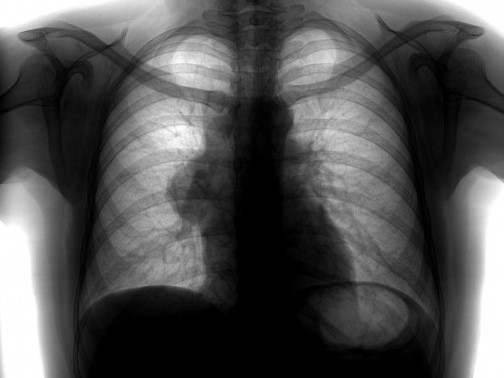

Рентгенологический метод является основным для визуализации новообразования средостения. Компьютерная томография позволяет оценить локализацию опухоли и спланировать дальнейшее обследование.